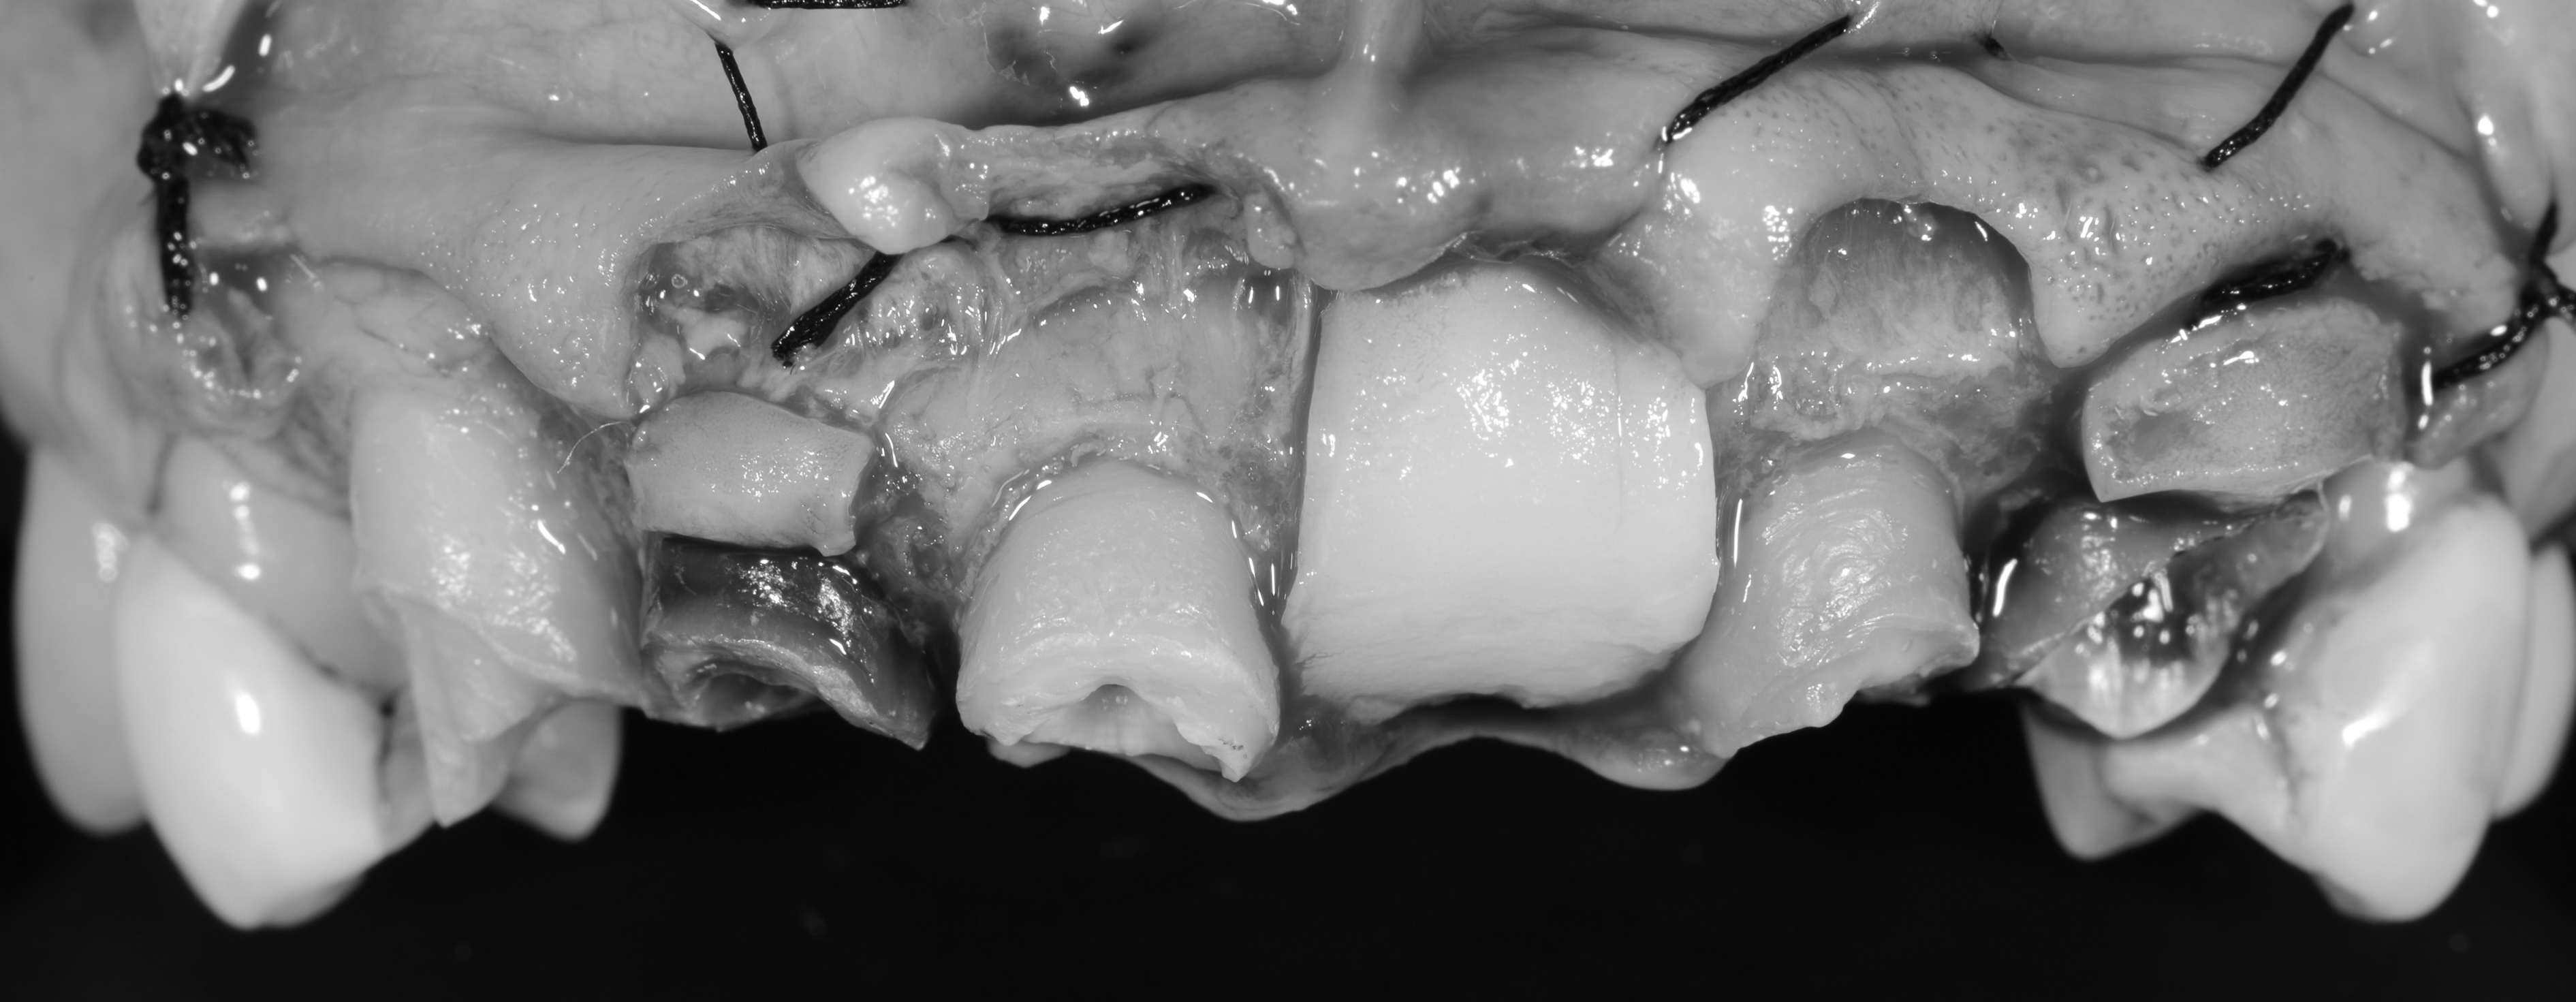

歯冠長延長術で歯を保存した上で審美性も改善した症例

- 年代、性別 53歳・女性

- 来院動機 インプラントにはしたくない

- 治療内容 精密根管治療、クラウンレングスニング